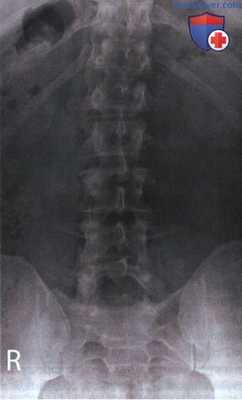

РИСУНОК 1 Рентгенограмма поясничного отдела позвоночника в ПЗ проекции, демонстрирующая правильное его расположение.

• Сколиоз: рис. 4 и 5

РИСУНОК 2 Правильное положение пациента для рентгенографии поясничного отдела позвоночника в ПЗ проекции. РИСУНОК 3 Рентгенограмма поясничного отдела позвоночника в ПЗ проекции. Левая сторона располагалась к ПИ ближе, чем правая.

РИСУНОК 4 Рентгенограмма поясничного отдела позвоноч ника в ПЗ проекции при выраженном сколиозе. РИСУНОК 5 Рентгенограмма поясничного отдела позвоночника в ПЗ проекции при слабом сколиозе. РИСУНОК 6 Рентгенограммы поясничного отдела позвоночника пациента в боковой и ПЗ проекциях. Показано положение межпозвонковых щелей. РИСУНОК 7 Положение ЦЛ и поясничных позвонков при разогнутых нижних конечностях. РИСУНОК 8 Рентгенограмма поясничного отдела позвоночника в ПЗ проекции при разогнутых тазобедренных и коленных суставах. РИСУНОК 9 Положение ЦЛ и поясничных позвонков при согнутых нижних конечностях.

в) Сколиоз. Тела поясничных позвонков также могут казаться ротированными при сколиозе. Выраженный сколиоз (рис. 4) отличить от ротации достаточно легко в отличие от небольшого сколиоза (рис. 5). Несмотря на то, что как при сколиозе, так и при ротации расстояние между корнями дут позвонков и остистыми отростками будет разным, существуют определенные признаки, по которым оба состояния можно различить.

Так, при ротации продольная ось позвоночного столба остается прямой, а при сколиозе позвоночный столб отклоняется вбок. Если на рентгенограмме поясничные позвонки ротированы, это могло произойти вследствие ротации верха или низа туловища.

Средние поясничные позвонки (L3 и L4) могут быть ротированы только при ротации нижних грудных, верхних или нижних поясничных позвонков. Напротив, при сколиозе на рентгенограмме могут быть ротированы только средние поясничные позвонки.